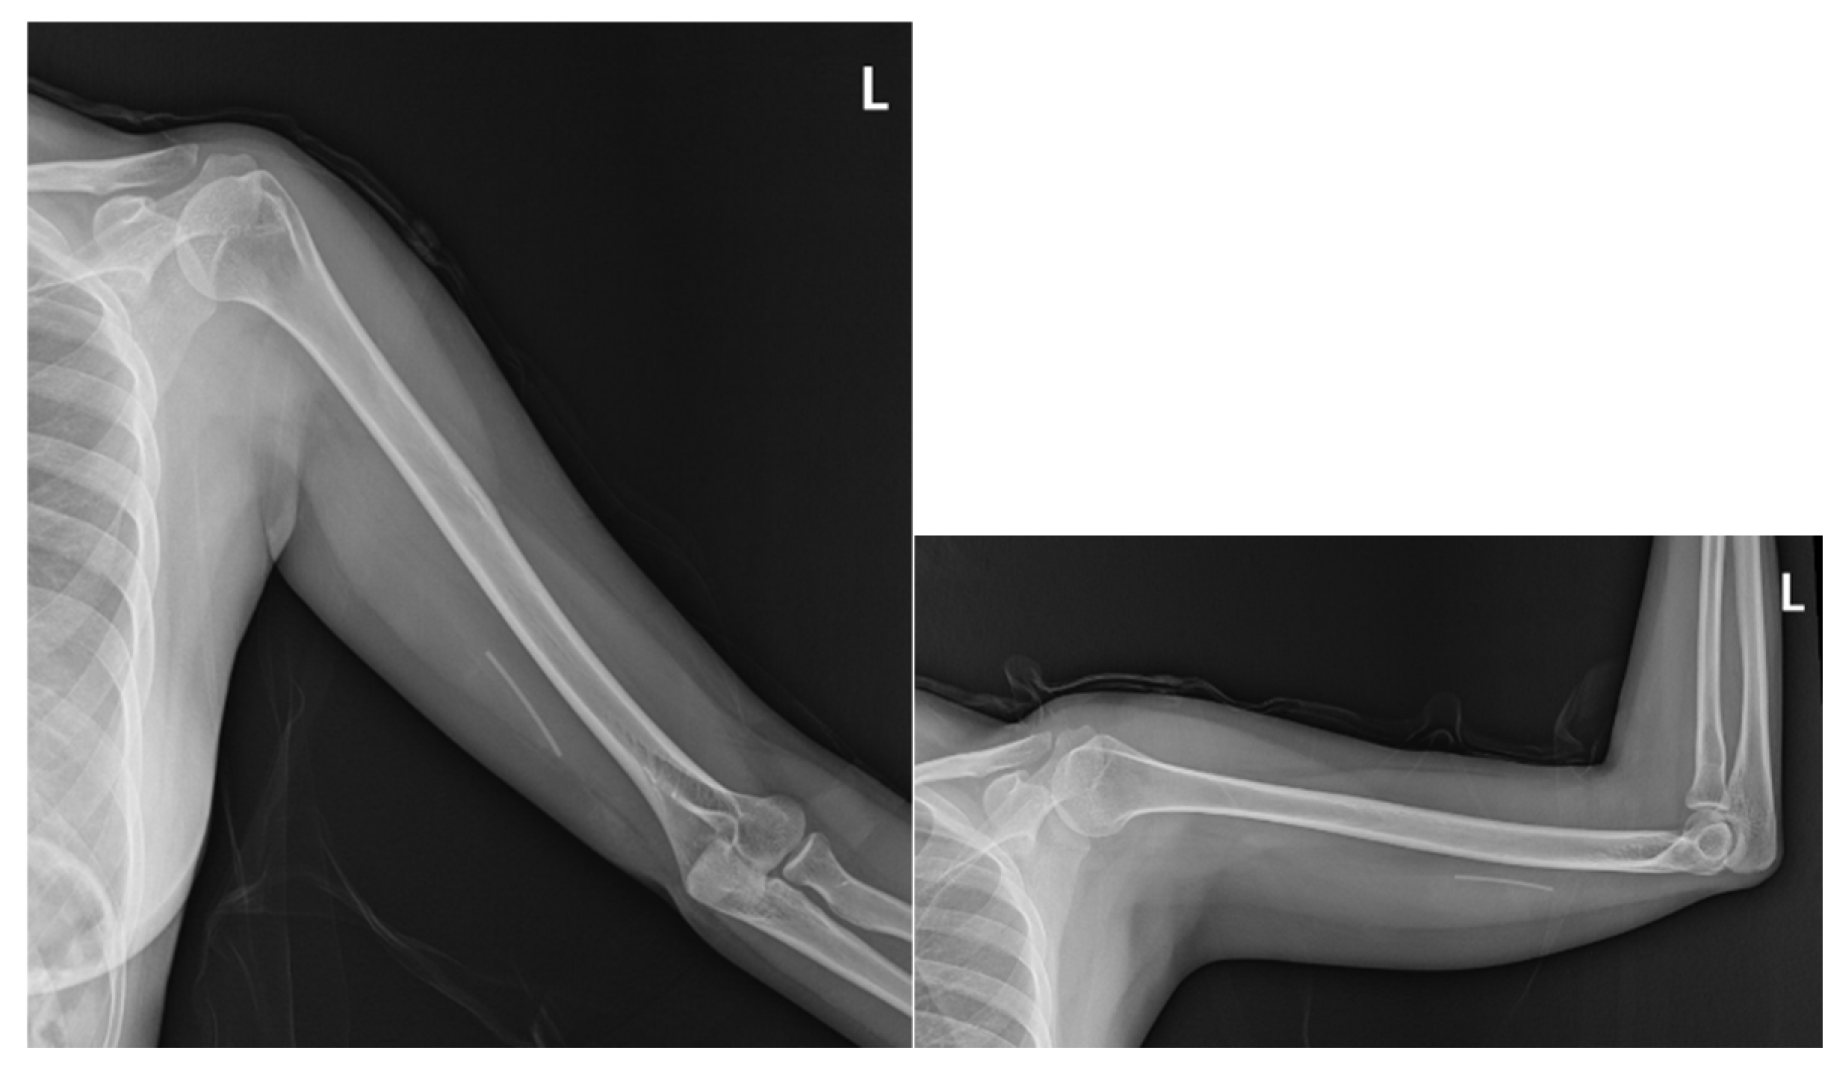

2.1. Prior Imaging Included Radiography (Figure 3) Confirming Implant Location, and Ultrasound (Figure 4) Demonstrating Its Adjacency to the Ulnar Nerve

Plain radiography of the left arm revealed no bony deformities or structural abnormalities accounting for her neurological symptoms. However, imaging demonstrated a linear radiopaque structure consistent with the residual Implanon device in the medial aspect of the arm (Figure 3).

Figure 3. Plain radiograph of the left arm showing a linear radiopaque structure consistent with the retained Implanon® device. No bony deformities or structural abnormalities were noted that could account for her neurological symptoms.

Preprints 171941 g003